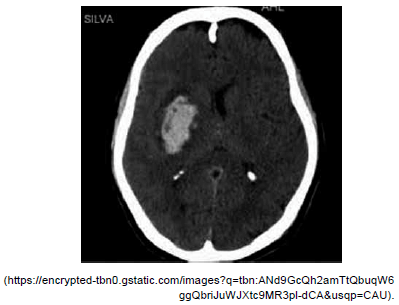

Paciente masculino, 62 anos, hipertenso sem controle adequado, admitido com quadro súbito de hemiplegia completa à direita, afasia de expressão, desvio do olhar conjugado para a direita e discreto rebaixamento do nível de consciência. Na admissão, apresentava-se afebril, glicemia capilar 98 mg/dL, PA: 190x100 mmHg e pontuação na escala do NIH de 13.

Assinale a alternativa correta quanto à conduta inicial adequada no controle pressórico desse paciente.